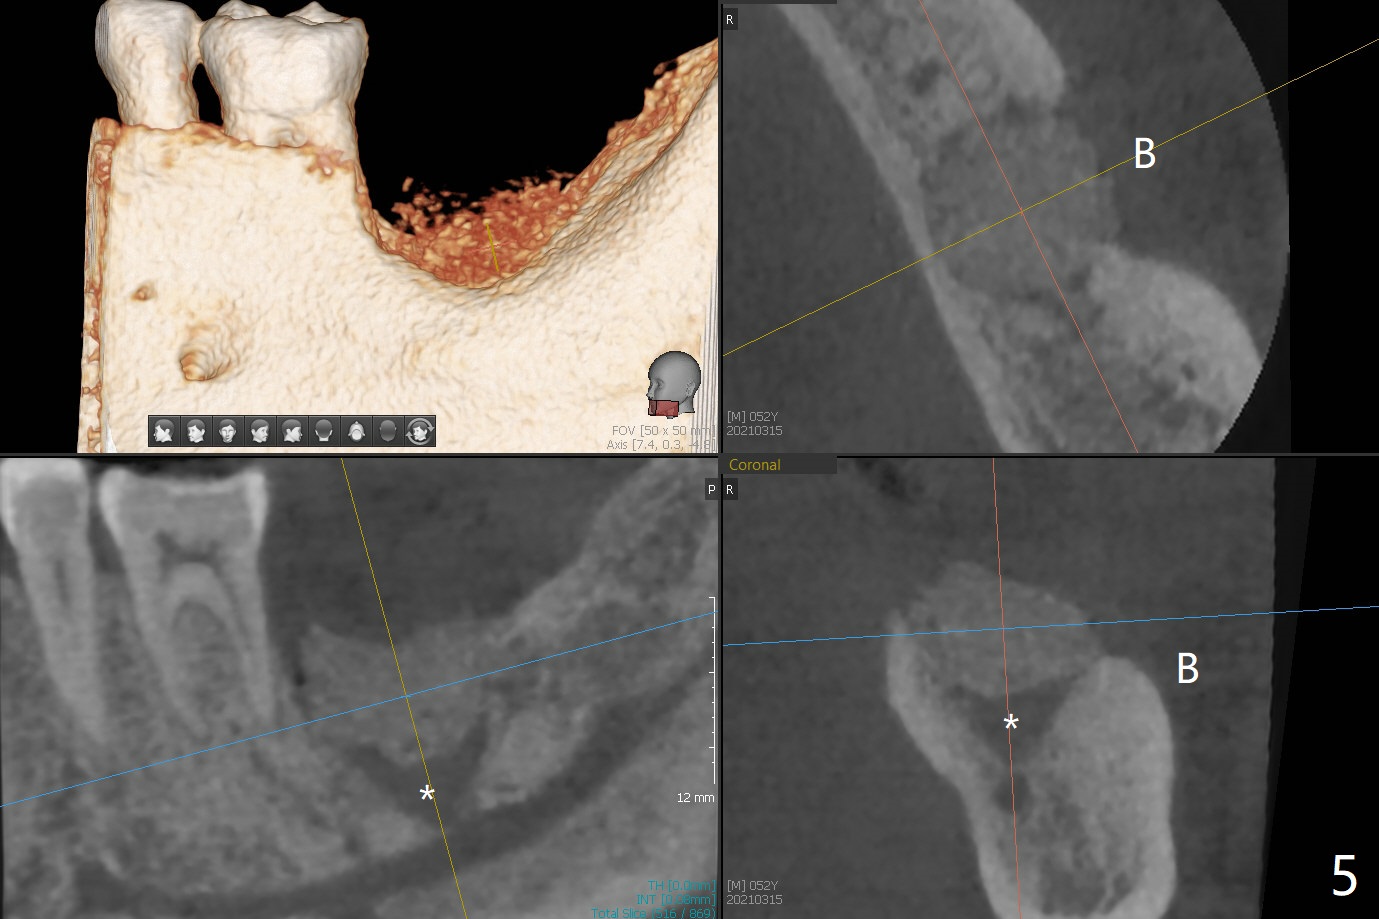

52岁男要求拔除松动左下7(图一,二),同意植骨,我们需要注意什么?我一般在类似情况下,使用浸润麻醉,但是今天改用block anesthesia,加浸润麻醉,直接将局麻药注射于牙龈,疼痛和出血控制好(图三:G(含有肾上腺素纱布)),麻醉方面有什么缺点?我不喜欢block anesthesia,万一碰到神经,麻醉深,病人不会给提醒。牙槽窝近中舌侧远中骨壁肉芽组织彻底清除;由于视野不好,切开(图四),牙槽窝底部*是软的,敢去除吗?其实我第一次向软组织投降,不敢去除,好像挺容易出血,接着敢植骨吗?其实植入粘性骨粉(皮质骨),术后CT检查表明遗留肉芽组织(图五:*),大约4毫米厚(图六),病人身体现在可忙乎了。覆盖PRF膜和不可吸收膜各一张,4-0 PTFE缝合,开口基本关闭,最后使用树脂敷料。